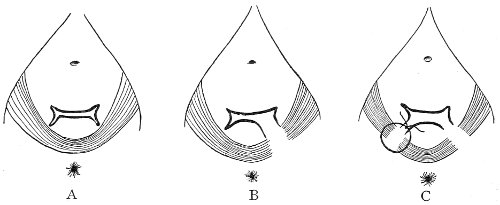

Slight Median laceration of the Perineum.—In this injury the tear takes place through the fourchette. Posteriorly it may extend as far as the sphincter ani muscle. Upward it may extend for an inch up the posterior vaginal wall. The appearance of this tear is shown in Fig. 33. It will be noted that, as this tear takes place in the median line, none of the muscles that support the perineum are involved, nor are the planes of fascia injured. The perineum is slightly split, and the insertions and origins of the muscles and the fascia are slightly separated. The supporting structures of the perineum and the pelvic floor are, however, uninjured.

Fig. 33.—Recent slight median laceration of the perineum: sutures introduced.

If this tear is detected after labor, it should be closed by the immediate operation. A slight tear involving chiefly the cutaneous aspect of the perineum should be closed by three or four sutures introduced from the outside, as in Fig. 33. The needle should be introduced about a quarter of an inch from the edge of the wound. It should not be passed parallel with the plane of the lacerated surface, but should be swept outward and then inward toward the 68 angle at the bottom of the tear (Fig. 34). It may either emerge at the angle and be re-introduced, or it may be passed directly through to the skin-margin on the opposite side of the wound. If the suture is passed in this way, there will be perfect apposition throughout the whole surface of laceration. If the sutures are improperly passed, there may result only apposition of the skin-edges.

Fig. 34.—Diagram representing the correct and the incorrect method of passing the suture for closure of slight perineal laceration.

If the laceration extends up the posterior vaginal wall, two sets of sutures must be introduced—one on the vaginal aspect of the tear, and one on the skin aspect (Fig. 35).